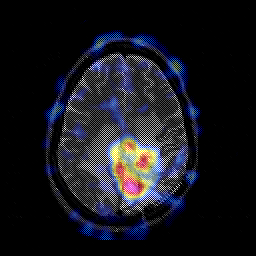

Glioblastoma multiforme overlay -- Slice #37

[Home][Help][Clinical][Tour 1][Tour 2][Tour 3] Slice 37